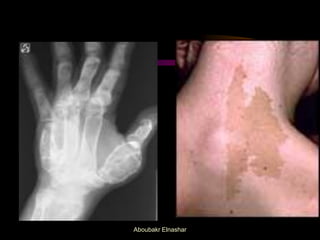

Albright S (precocious puberty, café-au-lait skin patches, cystic bony changes).

d. X ray of the lower ends of radius & ulna:bone age

1. Isosexual: FeminizingT (Granulosa-Theca cell, malignant teratoma). Estrogen intake. Albright S (precocious puberty, café-au-lait skin patches, cystic bony changes). Hypothyroidism (Short stature & retarded bone age). Aboubakr Elnashar